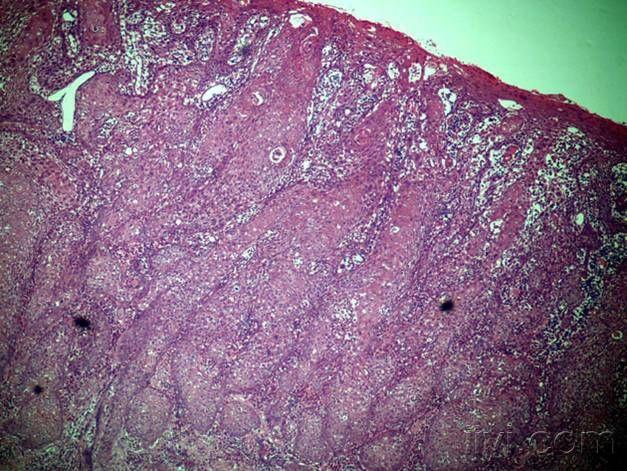

医生:大多数囊肿不用处理,但若出现在这3个地方,需要提高警惕